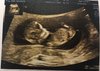

Kobitki, melduje się po badaniu- Wszystko jest super!

Kość nosowa obecna, przeziernosc karku 1,30mm. I wszystkie inne pomiary tez dobre.

Zmienił nam się tp, z 19 na 15 maja [emoji4]

Bardzo niskie ryzyko, ale pappa tez musiałam zrobic, mam nadzieje ze wszystko tam tez wyjdzie dobrze :)

Jestem tez już zapisana na drugie prenatalne na 18 grudnia, wtedy tez lekarz określi płeć, bo aktualnie sam stawiałby na chłopaka, ale nie da sobie ręki uciąć bo jest wczesnie i nie widać.

I Nasz robaczek [emoji173]️

IMG_8119.JPG